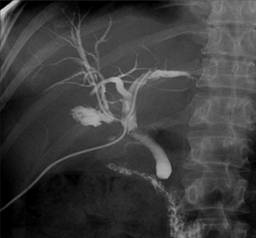

Lesiones iatrogénicas del conducto biliar, un problema complejo

Las lesiones iatrogénicas del conducto biliar (IBDI) siguen siendo un problema significativo en la cirugía gastrointestinal debido a la complejidad del sistema biliar y los riesgos asociados con su manejo…